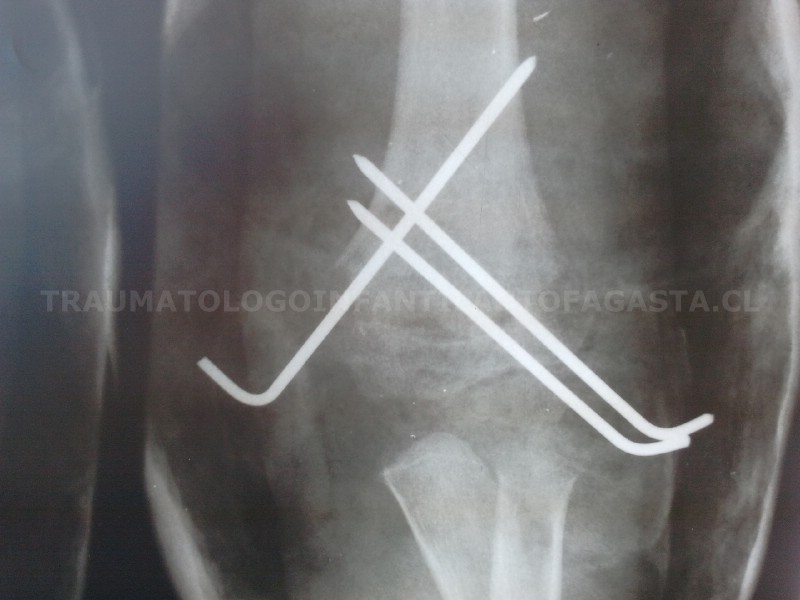

Fractura de codo inestable